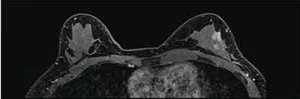

●Enhanced Fat FreeおよびMulti-phase Transmissionによる両側均一な脂肪抑制

3T MRIでは,B ,B1不均一による脂肪抑制ムラが懸念されています。Titan 3Tでは,安定した脂肪抑制の実現のため,

2発の脂肪抑制パルスを印加する脂肪抑制法“Enhanced Fat Free”および2ch 4port送信の新たなRF送信技術“Multi-phase Transmission”を搭載しています。これらの技術により,確実な脂肪抑制画像を提供することができます(図1)。

図1 Dynamic早期相

(画像ご提供:杏林大学医学部付属病院様)